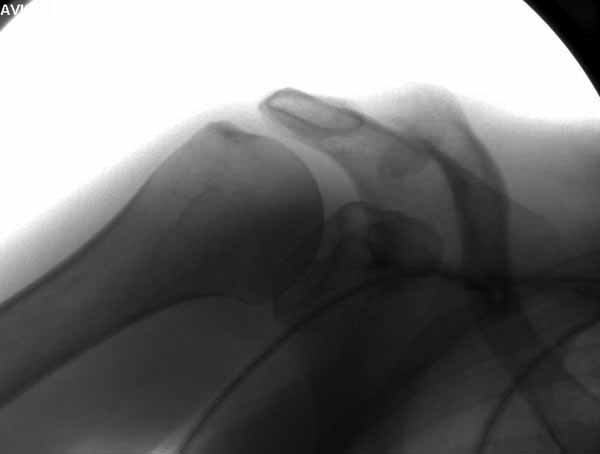

foto

2.JPG

12KB (12589 bytes)